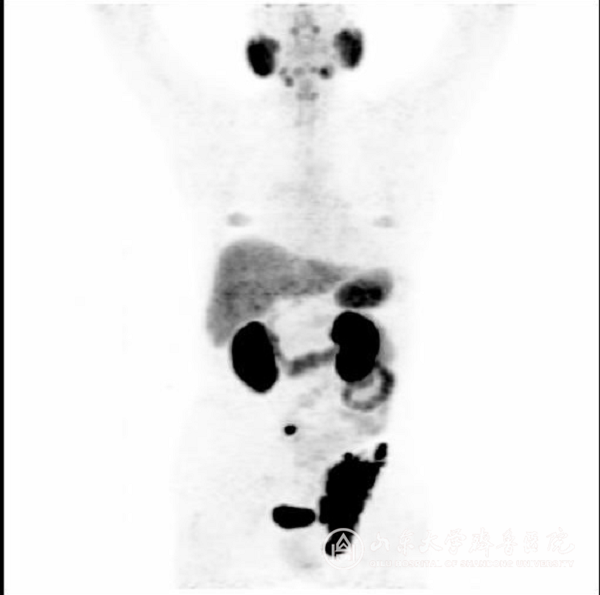

图5 显示前列腺癌患者多发转移

PET/CT(正电子发射型计算机断层显像)是目前最先进的分子影像精准诊断方法,一次检查,不仅可以清晰显示原发肿瘤病灶,而且全身各处的淋巴结转移、骨转移、肝转移或肺转移等病灶也无一遗漏,可以为临床医师提供最全面最精准的临床分期,对指导治疗意义重大。PSMA(前列腺特异性膜抗原)因为特异性的在前列腺癌细胞中高表达而成为检测前列腺癌的绝佳理想靶点。PSMA PET/CT显像显著提高了前列腺癌及其转移灶的诊断准确性。在欧美国家每年有数万名前列腺患者进行PSMA PET/CT检查,而国内仅有北上广等几家大绿帽社开展了该项检查。

PSMA PET/CT显像对于前列腺癌术前病人可以进行原发病灶的定位,指导穿刺活检;判断全身转移情况,精准临床分期;对于术后生化复发病人可以寻找复发及转移病灶,及时进行下一步治疗;对于PSA升高的患者,可以判断病灶性质,有助于早期诊断。此项技术真正是前列腺癌患者的新福音。